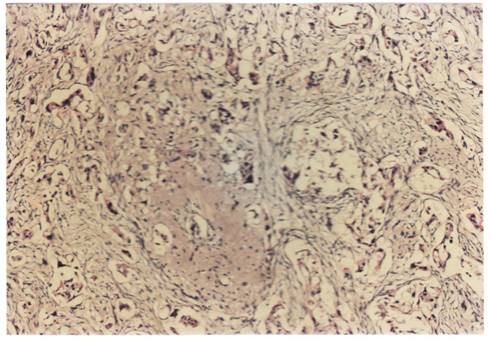

Criterii microscopice de diagnosticare a cancerului mamar

Pentru examenul histopatologic piesele de mamectomie sunt prelucrate prin imparafinare si colorate cu Hematoxilina-Eozina sau, pentru observarea mai buna a tesutului conjunctiv, cu Van Gieson.

Pe preparate colorate, la microscopul optic se observa urmatoarele imagini :